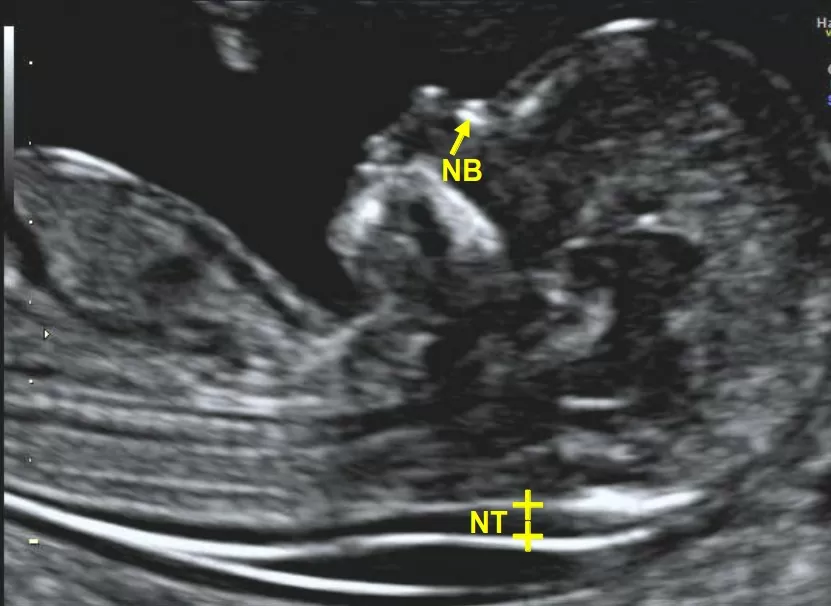

Lo studio della translucenza nucale (NT), in particolare, è stato promosso e diffuso dalla FMF con l’adozione di standard rigorosissimi e di elevata qualità.

Con il supporto di un team internazionale di esperti, la FMF ha introdotto alcuni certificati di competenza per i diversi ambiti della Medicina Fetale, come lo Screening per i difetti cromosomici, conosciuto meglio come Bi-Test o Ultra-Test (Ultra-Screen) che utilizza la misura della NT.

- Misurazione ecografica della Translucenza Nucale